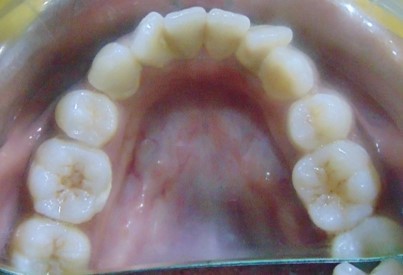

After

Image 2

Image 3